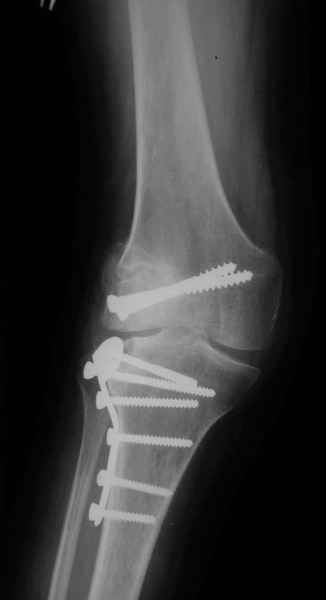

Как вариант решения прогрессирующей вальгусной деформации коленного сустава я бы предложил косую остеотомию дистального отдела бедра с фиксацией пластиной и компрессирующим винтом.

Взгляните на снимки , может быть это вам поможет.

Около 5 лет применяю этот тип дистальной остеотомии бедра для коррекции механической оси Н/К ( более 20 случаев) - достаточно эффективная операция.

Уважаемый Евгений ! Спасибо за ответ, но мне представляется, что в нашем случае основной проблемой является не столько прогрессирующий вальгус конечности, сколько несросшийся перелом мыщелка бедра и дефект мыщелка большеберцой кости - вероятно первичная репозиция выполнялась без пластики.

На своем горьком опыте убедился, что синтезировать мыщелковые импрессионные внутрисуставные переломы б\б кости без костной пластики - дело неблагодарное, рецидивируе деформация, мыщелок всегда *проваливается*. Чистые split type переломы можно ограничиваться и одной только межфрагментарной компрессией.

Может стоит сначала добиться сращения наружного мыщелка бедра( костная пластика) и коррекции оси?

Мне представляется, что прогрессирующий вальгус и обусловлен несросшимся переломом мыщелка бедра (томограммы -зона межфрагментарного склерозирования), а циклические нагрузки на сустав во время ходьбы усугубляют ситуацию. Как вы думаете, в этой ситуации насколько вероятен риск развития аваскулярного некроза мыщелка бедра?